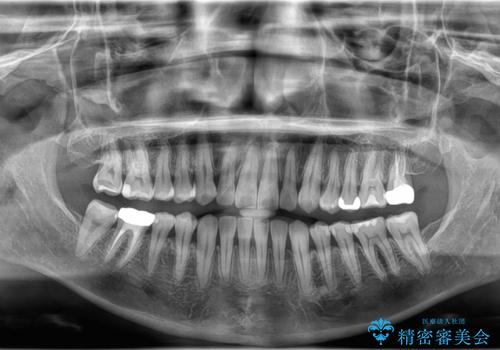

11ヵ月で矯正治療が終了し、前歯の隙間も改善、見た目とかみ合わせも良好な状態となり、患者様にも大変ご満足いただけました。

治療途中に海外へ転勤となりましたが、インビザラインは海外在住の方や転勤が多い方でも継続しやすい治療方法です。